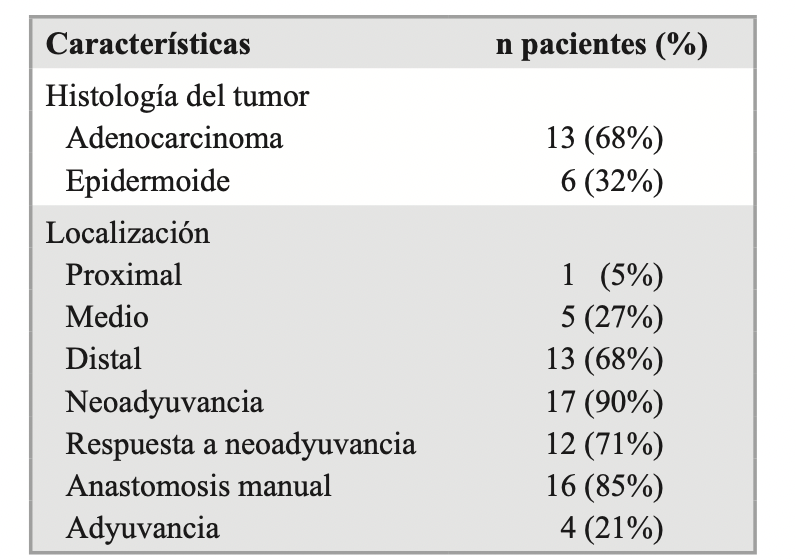

Rocío Forneiro Pérez, Juan Alfredo Ubiña Martínez, Inmaculada Lendínez Romero

|

|